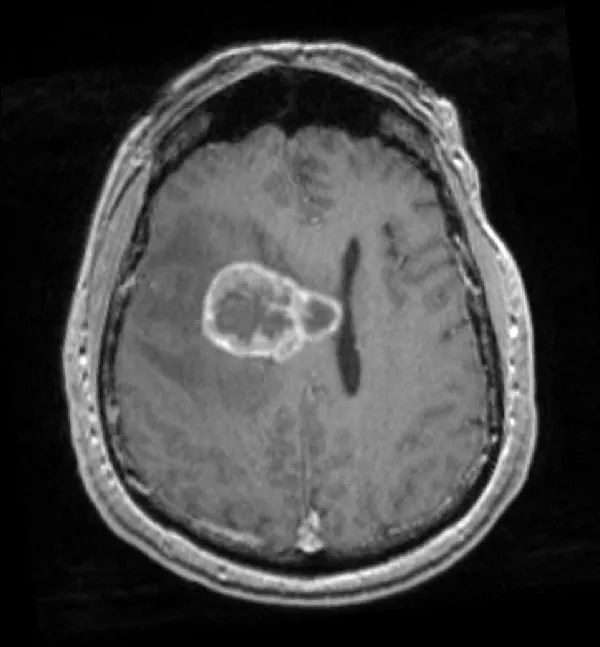

患者为55岁男性,因“跌倒频率增加和左侧肢体无力1周余”就诊。 3年前患者曾于外院行肺癌切除术,但患者后来失访,且无法明确癌变性质和分期。 入院时神经系统查体无异常。 外院头颅CT见颅内出血灶,胸腹盆腔CT未见异常。 立体定向颅内病变活检提示肿瘤为低分化转移癌,细胞标志物检测考虑鳞状细胞癌。

立体定向导航下行右额开颅。 鉴于肿瘤位置深,计划在60mm长BrainPath(厂家NICO)管型牵开器辅助下以微侵袭方式切除该肿瘤。 术前借助导航系统于右侧额叶寻找对应肿瘤长轴的脑沟并以此为进入点确定术中路径,手术通道与肿瘤长轴平行可以有效降低纤维传导束和基底节的损伤风险。

右额开颅最重要的注意事项就是骨瓣应该位于冠状缝前方以防误伤中央前回。 如果患者为左利手,应避开额下回,尤其三角部和盖部,以免损伤Broca区。 肿瘤尾端侵犯尾状核、内囊前肢和侧脑室额角,部分肿瘤已经毗邻室间孔,因此可能与穹窿、丘纹静脉和尾状核静脉关系密切。

术后患者安返神经ICU。 术后使用地塞米松并于1周内迅速减量撤药。 使用左乙拉西坦500mg bid预防性抗癫痫。 术后第1天复查MRI见肿瘤近全切。